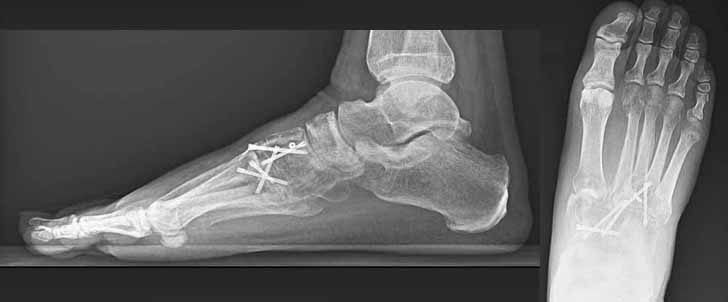

Imatge de radiografia convencional (dreta) i TAC (esquerra) d’unes fractures que afecten l’anomenada articulació de Lisfranc, que comprèn les articulacions del mitjà peu entre les cuixes i els metatarsians. Es tracta de fractures desplaçades que requeriran cirurgia.

Radiografies postoperatòries de l’anterior pacient. Mitjançant cirurgia oberta es va realitzar la reducció de les fractures i es van implantar uns cargols per mantenir la reducció fins a la curació.